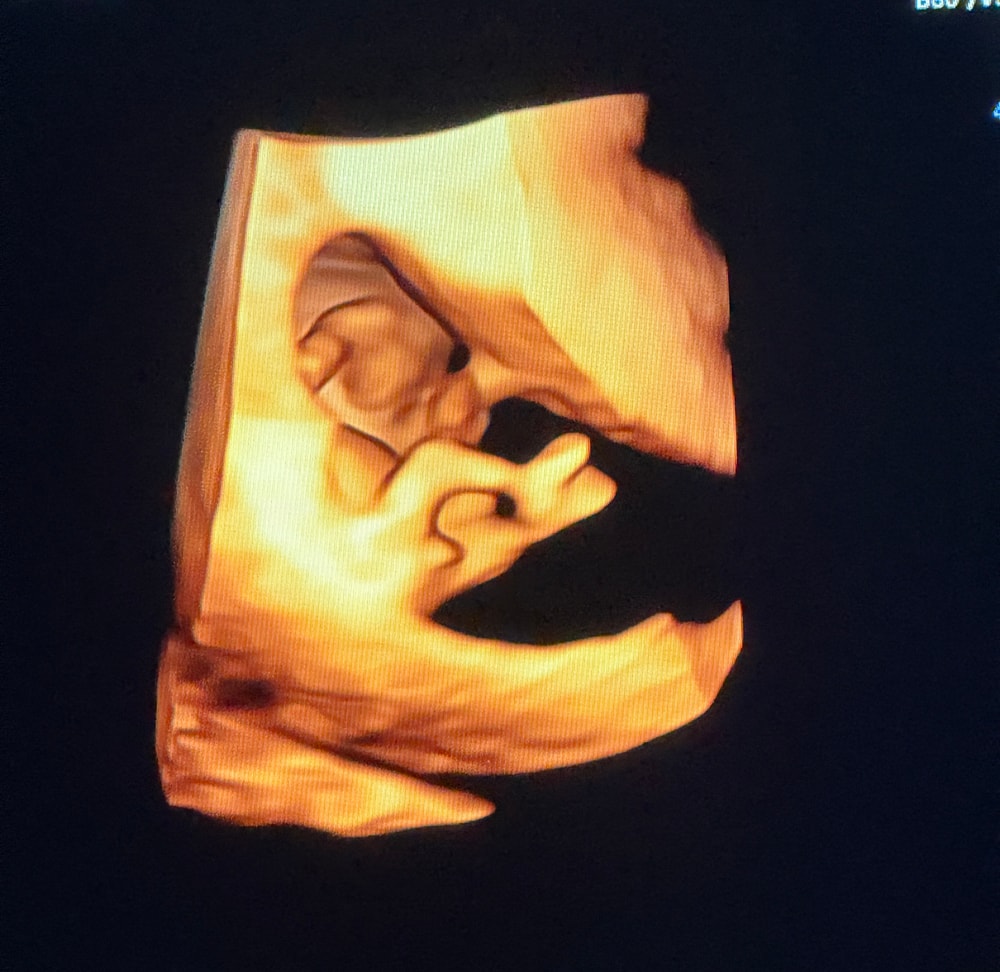

11.6 недель, предположили пол

Всем привет, сегодня предположили женский пол на узи, интересно стороннее мнение, нипт через 2 недели только прийдет. Что думаете? Сказали 90% девочка, 10% мальчик тк в 3D что-то выпирало😄

На этом сроке у всех выпирает, отличается только угол. Половые органы формируются к 16 неделям. Я бы тоже сказала, что девочка.